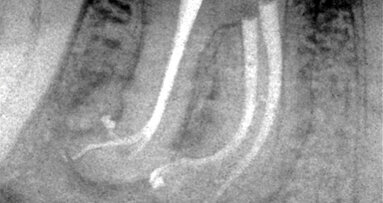

When one considers that relieved reamers are used in a way that assures long life, virtually eliminating separation, give the dentist more accurate information to determine how wide the canals should be shaped to, have the flexibility to be used both manually and in the reciprocating handpiece and is supported by a growing body of research that clearly demonstrates superior results are attainable while reducing costs per use by 90 percent compared to rotary NiTi, it is no surprise this alternative approach is garnering more and more enthusiastic attention. Clinical examples are shown in figures 5-7.